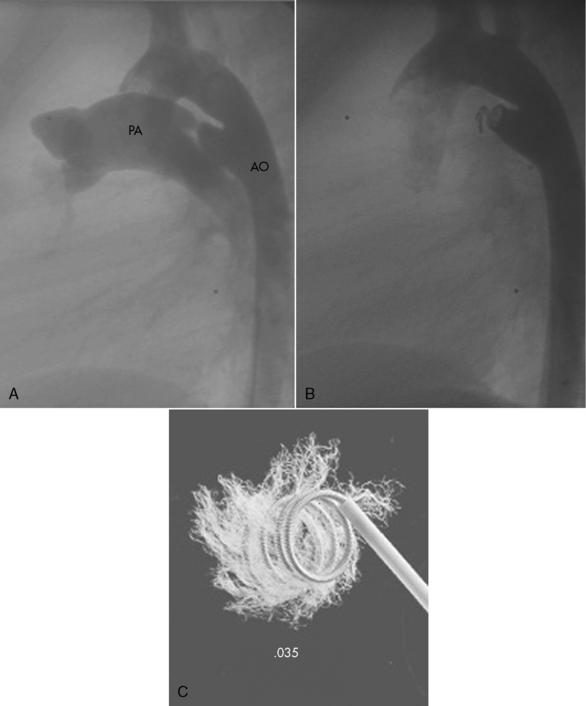

Coronary Artery Fistulas

Fistulas are the most common type of hemodynamically significant coronary anomalies; they can be congenital or acquired. Fistulas can be isolated or can occur in combination with other heart defects.242 They can involve the right (most common), left, or both coronary arteries.497 The fistulous connection can involve a coronary vein, a vena cava, a chamber of the heart, a great artery, pulmonary vessels, or an aorto-left ventricular tunnel.242,446,456,497

A fistula produces shunting of flow from the higher pressure to the lower pressure end of the fistula. The most common type of fistula is a coronary artery to right-heart structure (arteriovenous) fistula, which results in a left-to-right shunt.497 When the fistula connects to a left heart structure (arterioarterial fistula) there may be runoff from the aorta during low pressure phases of the cardiac cycle; this runoff can increase left ventricular volume load.497

The ECG and chest radiograph may be normal or may provide suggestive but nonspecific evidence. Echocardiography may establish the diagnosis, particularly if the fistula is large. Cardiac catheterization can provide the definitive diagnosis with aortography and selective coronary angiograms.336,497 Endocarditis and aneurysm with rupture have been reported with this lesion.456

In rare cases, spontaneous closure of a fistula has been reported. Intervention is recommended only if symptoms are present. In some cases coil occlusion of the fistula is possible during cardiac catheterization. Otherwise, surgery is performed through a median sternotomy incision and usually requires cardiopulmonary bypass. The fistula is identified, approached through the vessel or chamber, and sutures are used to close the connection. Without treatment the natural history of these defects has not been clearly determined, but surgical and hospital mortality, rate of complications, and late mortality are all very low.497